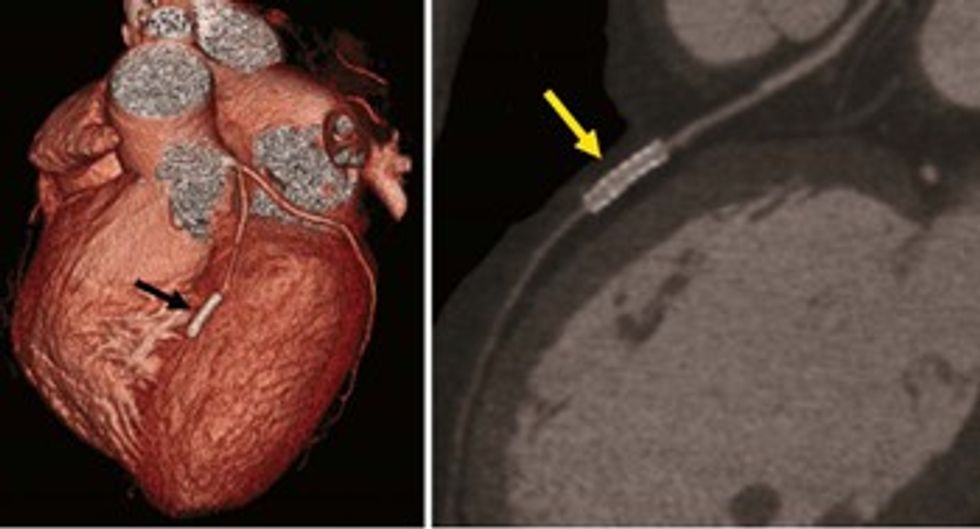

Me koronarografi me tomografi të kompjuterizuar mund ta shohim zemrën në tërësi nga të gjitha anët, ku shohim muret e saj të formuara nga muskuli i zemrës dhe arteriet koronare në sipërfaqe.

Mund t’i analizojmë ndaras arteriet koronare dhe ta vlerësojmë patologjinë e tyre të mundshme.

Poashtu në masë të caktuar me koronarografi me tomografi të kompjuterizuar mund të analizohet edhe kalueshmëria e stenteve të vendosuara në arteriet koronare.